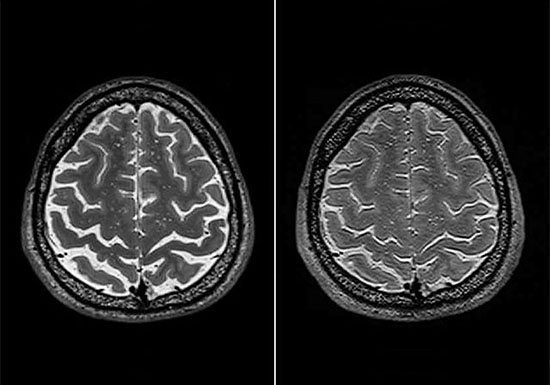

また最近、アメリカ・サウスカロライナ医科大学が、宇宙での滞在が脳の解剖学的構造に与える影響を画像診断で調査した結果を発表しました。それによると、5カ月以上の長期にわたって宇宙に滞在した宇宙飛行士のほぼ全員に、脳の隙間が部分的に小さくなったり脳が頭蓋の中で上方にずれたりしているケースが認められたそうです。

宇宙に長期滞在した宇宙飛行士の脳のMRI画像(左:出発前 右:地球帰還後)(出典=「Effects of Spaceflight on Astronaut Brain Structure as Indicated on MRI」)

宇宙に長期滞在した宇宙飛行士の脳のMRI画像(左:出発前 右:地球帰還後)(出典=「Effects of Spaceflight on Astronaut Brain Structure as Indicated on MRI」)『宇宙と地球を視る人工衛星100 スプートニク1号からひまわり、ハッブル、WMAP、スターダスト、はやぶさ、みちびきまで』 地球の軌道上には数多くの人工衛星があり、私たちの生活や地球・宇宙の解明に役立てられています。 本書ではこれら人工衛星の基本的な仕組みから歴史、そして100の代表的な人工衛星の概略とその役割を解説していきます。